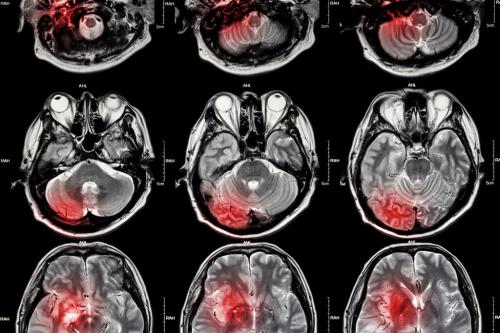

Diffüzyon MR

MR da vücudumuzdaki hidrojen protonları uyarılarak sinyal alınır. Sıvı yoğun ortamda hidrojen protonları hareketli olur, bu hareket diffüzyo...